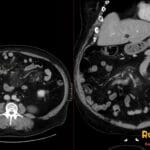

- Radiology Cases: Images with a to-the-point discussion highlighting the specific diagnostic criteria.

Latest Radiology Cases